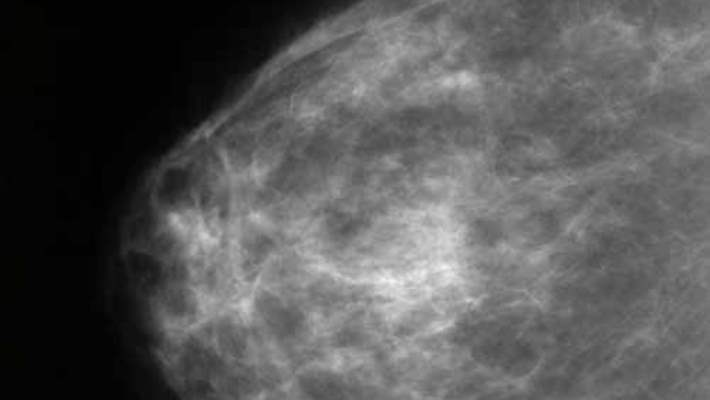

Mamografi, göğüs kanseri taraması için kullanılan ve göğsünüzün siyah-beyaz bir görüntüsü alan bir yöntemdir. Mamografi, göğüs kanserinin erken teşhisinde önemli bir rol oynar; bu sayede göğüs kanserinden kaynaklanan ölümlerin azalmasına da büyük ölçüde yardımcı olur.

Mamografi uygulamasında göğüs dokusunu yaymak için göğsünüz, iki sertleştirici yüzey arasında sıkıştırılır. Ardından bir röntgen cihazı yardımıyla doktorunuzun, göğüs bölgenizdeki değişiklikleri ve kanser belirtilerini araştırırken kullanacağı röntgen resimleri çekilir.

Mamografi, göğüs dokunuzun X-ray film üzerindeki siyah-beyaz fotoğrafı şeklinde mamogram’lar elde edilmesini sağlar. Eğer dijital mamografi kullanılmışsa, sonuçlar elektronik bir monitör yardımıyla görüntülenir veya incelenmek üzere çıktı alınabilir. Elde edilen görüntüler bir radyoloji uzmanı tarafından yorumlanarak, bulgular yazılı bir rapor halinde doktorunuza gönderilir.

Radyoloji uzmanı incelemelerinde takip, tedavi veya yeni testler gerekebilecek, kanser veya kanser olmayan (iyi huylu) oluşumlara dair kanıtlar arar.